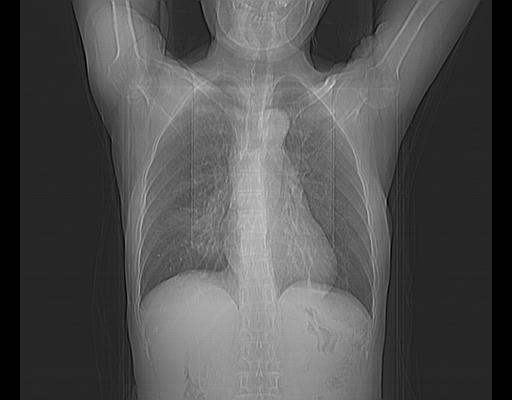

CT50279:女,73岁,咳嗽、咳痰伴胸痛。8598

右肺脓肿

右肺感染性病变伴脓肿形成

右下肺脓肿,左下肺大疱。